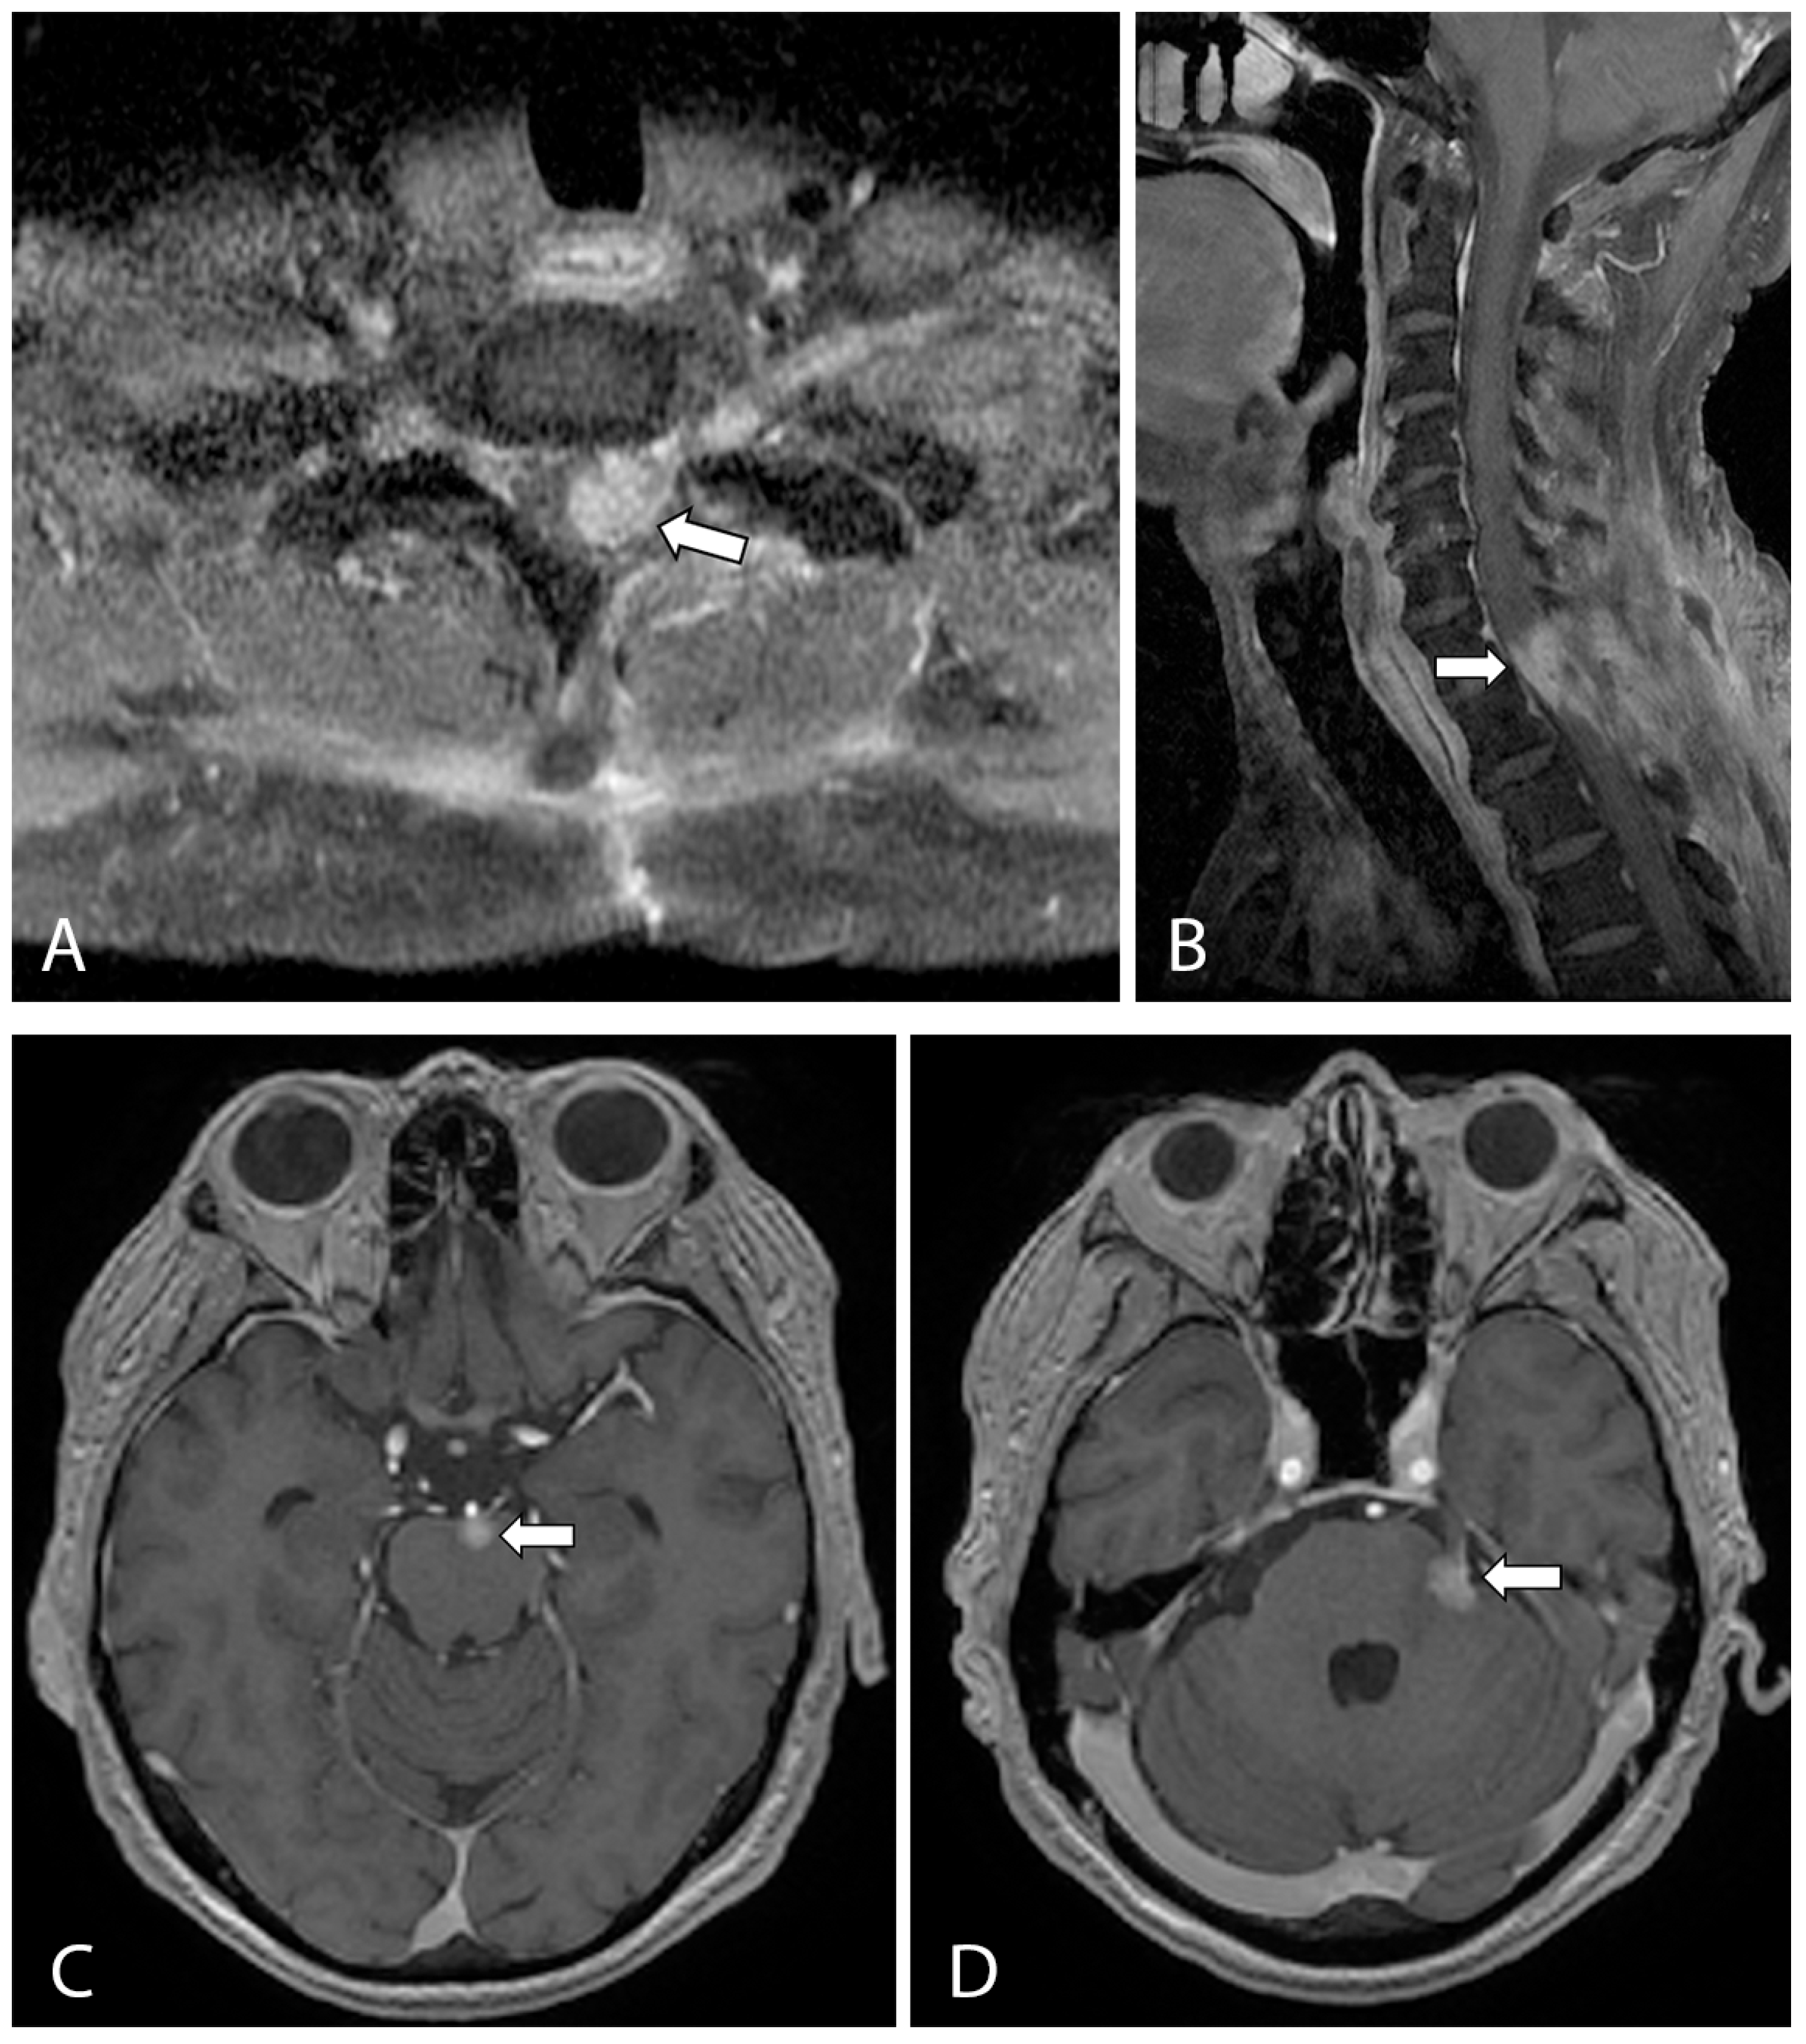

2. Case Presentation